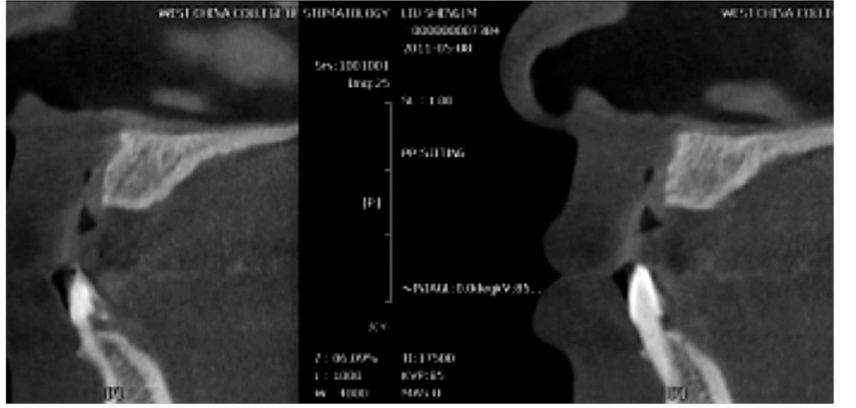

图7 术前矢状位

CBCT片显示牙槽骨密度低,正在愈合中

图8 术后CBCT片矢状位

显示种植体植入5个月后2期修复前的状况

图9 术前术后矢状位CBCT片

A.牙槽骨密度及高度长度均好;B.显示种植体植入后的位置及高度良好